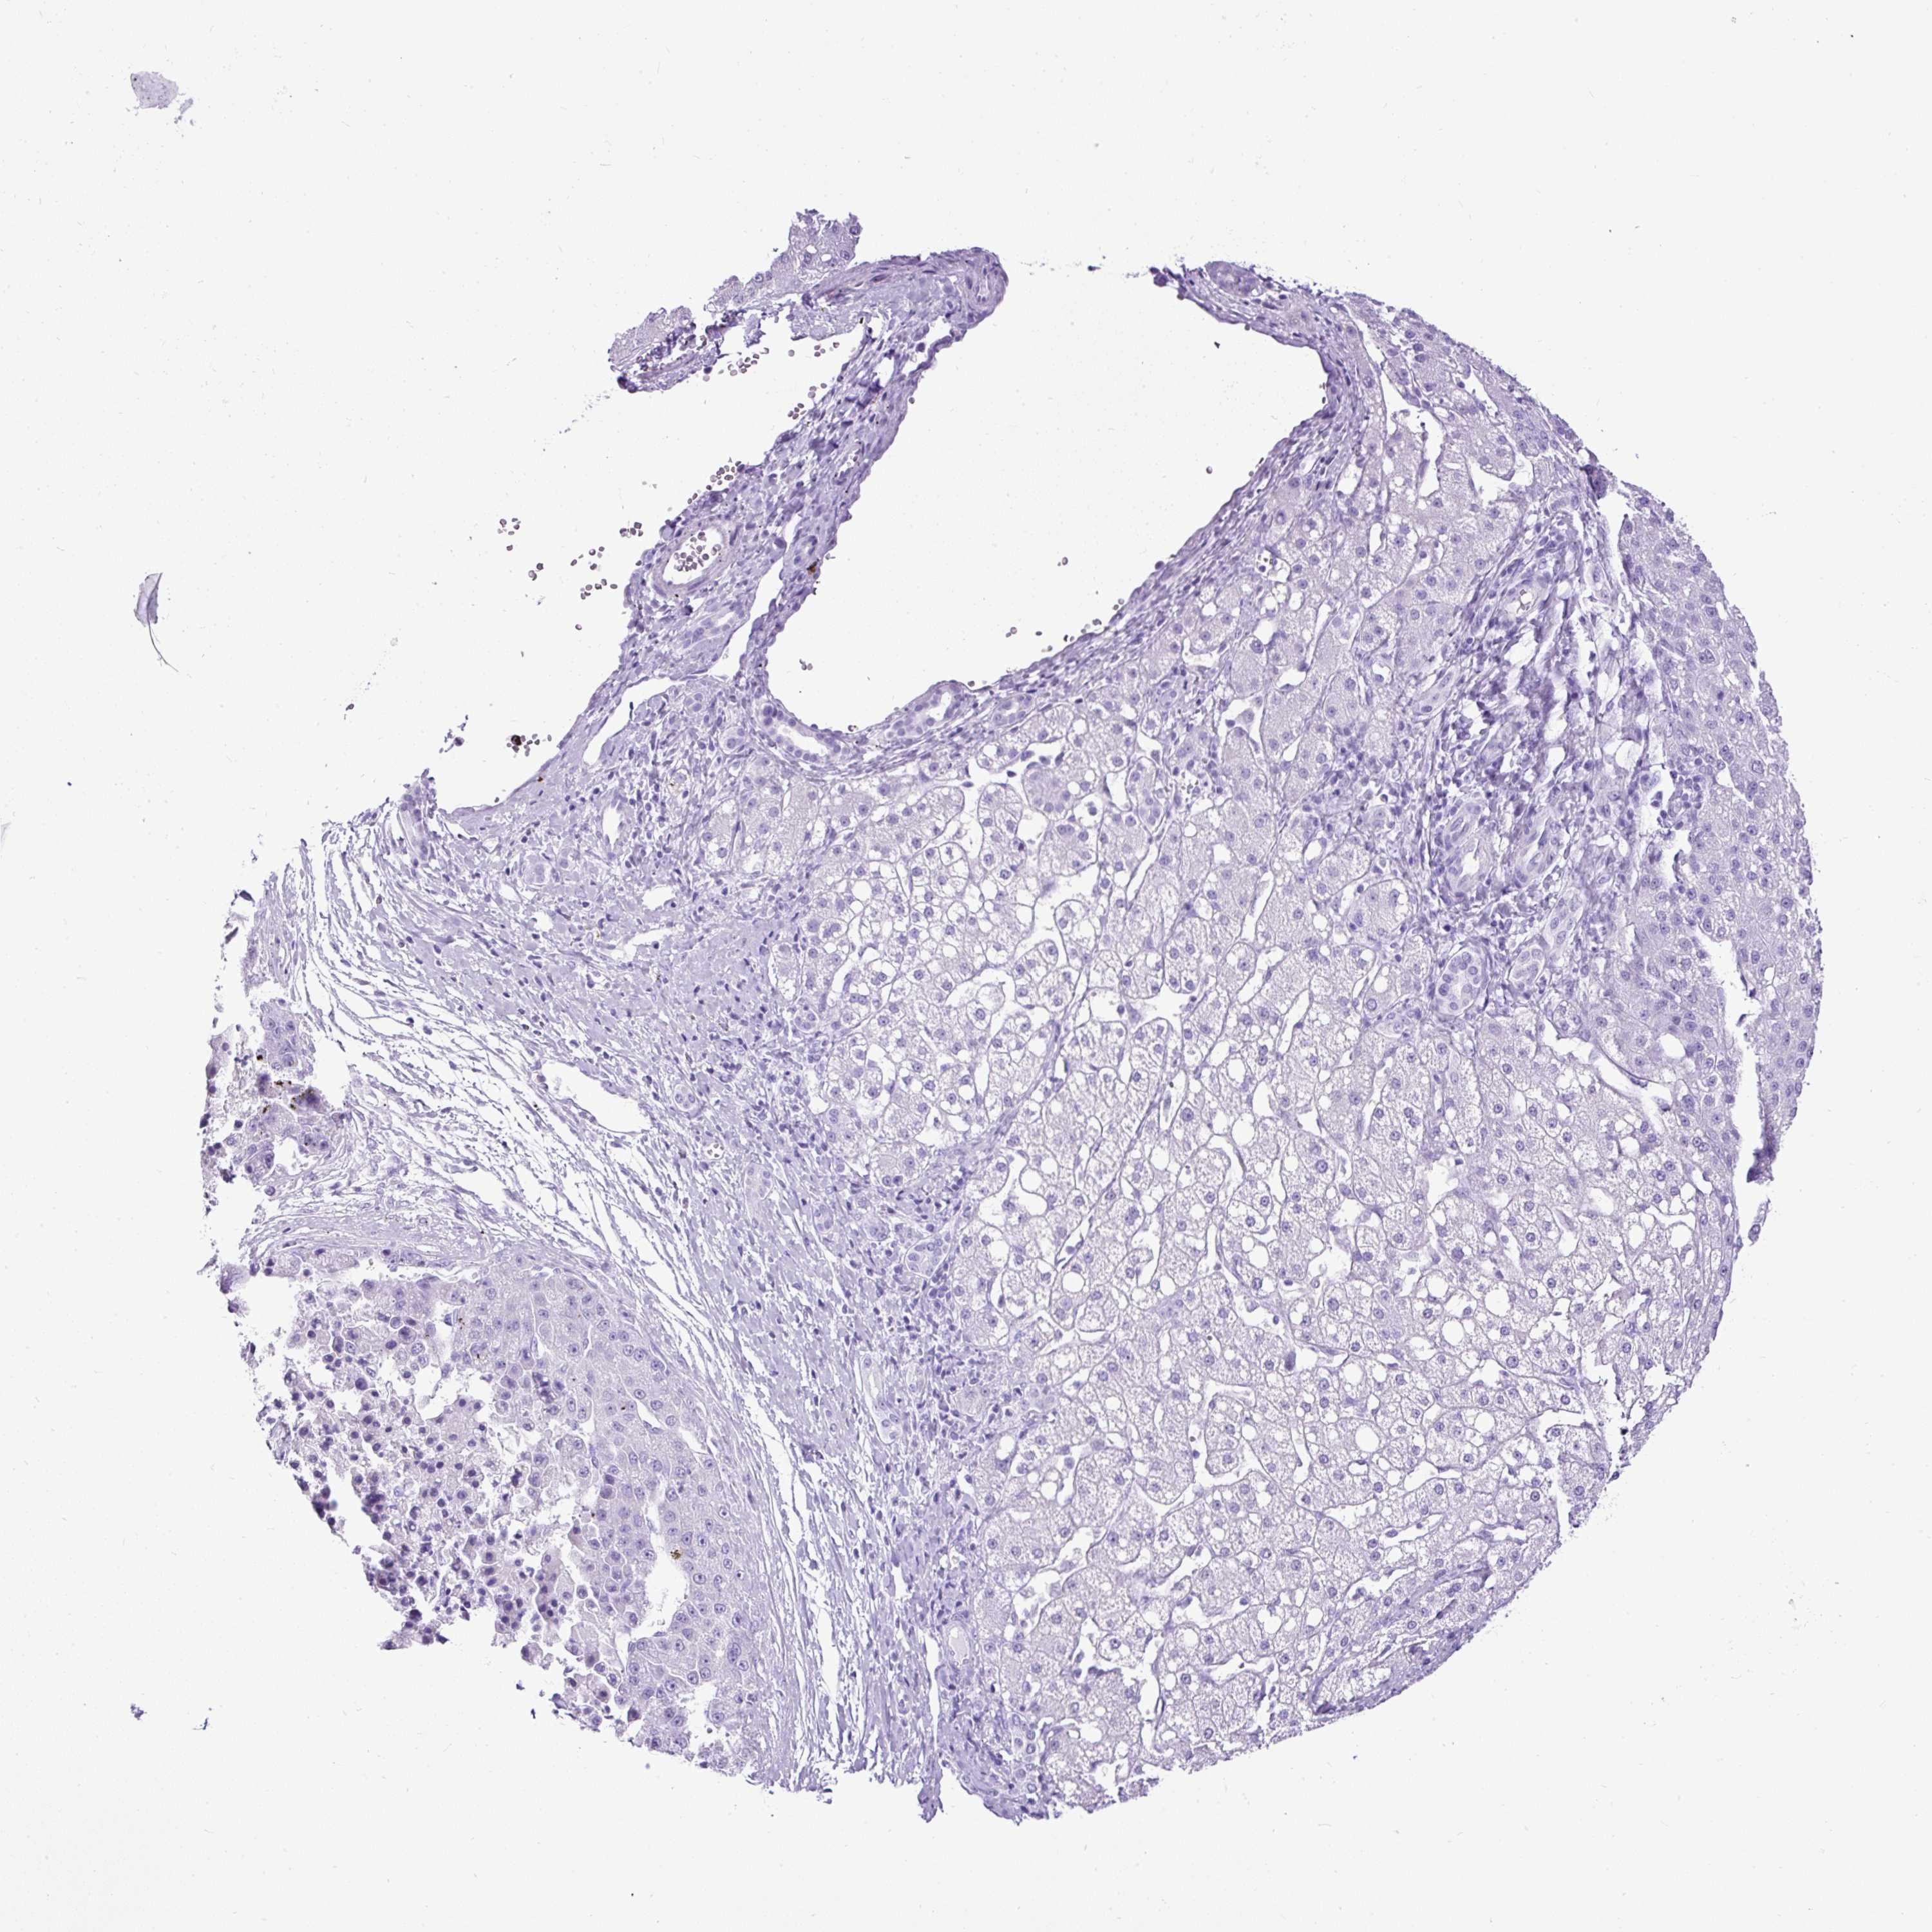

LIVER CANCER - Protein expressioni

A mouse-over function shows sample information and annotation data. Click on an image to view it in a full screen mode. Samples can be filtered based on level of antibody staining by selecting one or several of the following categories: high, medium, low and not detected. The assay and annotation is described here.

Note that samples used for immunohistochemistry by the Human Protein Atlas do not correspond to samples in the TCGA dataset.

Antibody stainingi

Antibody staining in the annotated cell types in the current human tissue is reported as not detected, low, medium, or high, based on conventional immunohistochemistry profiling in selected tissues. This score is based on the combination of the staining intensity and fraction of stained cells.

Each image is clickable and will lead to virtual microscopy that enables deeper exploration of all samples and also displays staining intensity scores, fraction scores and subcellular localization as well as patient and tissue information for each sample.

Antibody HPA008023

Antibody HPA052701

Staining

High

Medium

Low

Not detected

Intensity

Strong

Moderate

Weak

Negative

Quantity

>75%

75%-25%

<25%

None

Location

Nuclear

Cytoplasmic/membranous

Cytoplasmic/membranous,nuclear

Cholangiocarcinoma

Carcinoma, Hepatocellular, NOS